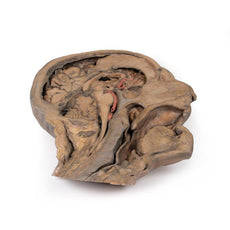

In the preserved midsagittal section there is preservation of the endocranial

contents, the nasal and oral cavities, and the pharynx to the level of the

laryngeal cartilages. The nasal cavity is preserved nearly intact, except for a

small window excised into the middle nasal concha to expose the ethmoid

air cells. A very large sphenoid sinus exists in the individual just superior

to the torus of the auditory tube in the nasopharynx. The oral cavity and

laryngopharynx are undissected, with the larynx only preserve just distal to the

level of the arytenoid cartilages and not including a clear set of vocal folds.

Within the endocranial cavity, the sectioned brain is slightly off the midagittal

plane, such that neither the superior sagittal sinus nor the third ventricle are

clearly defined - but the lateral ventricle is open and part of the fourth ventricle

is preserved between the pons and cerebellum. The gyri and sulci of the

cerebrum are not well separated, but the cingulate gyrus and corpus callosum

can be separated. Cross-sectioned views of the optic tract, pituitary gland,

superior and inferior colliculi, superior cerebellar peduncle, and transition

between the medulla oblongata and spinal cord are all visible. The tentorium

cerebelli and confluence/transverse sinus is positioned between the

cerebellar hemisphere and occipital lobe. Small portions of the posterior

inferior cerebellar artery, vertebral arteries, basilar artery, and posterior

cerebral and anterior cerebral arteries are visible in section.